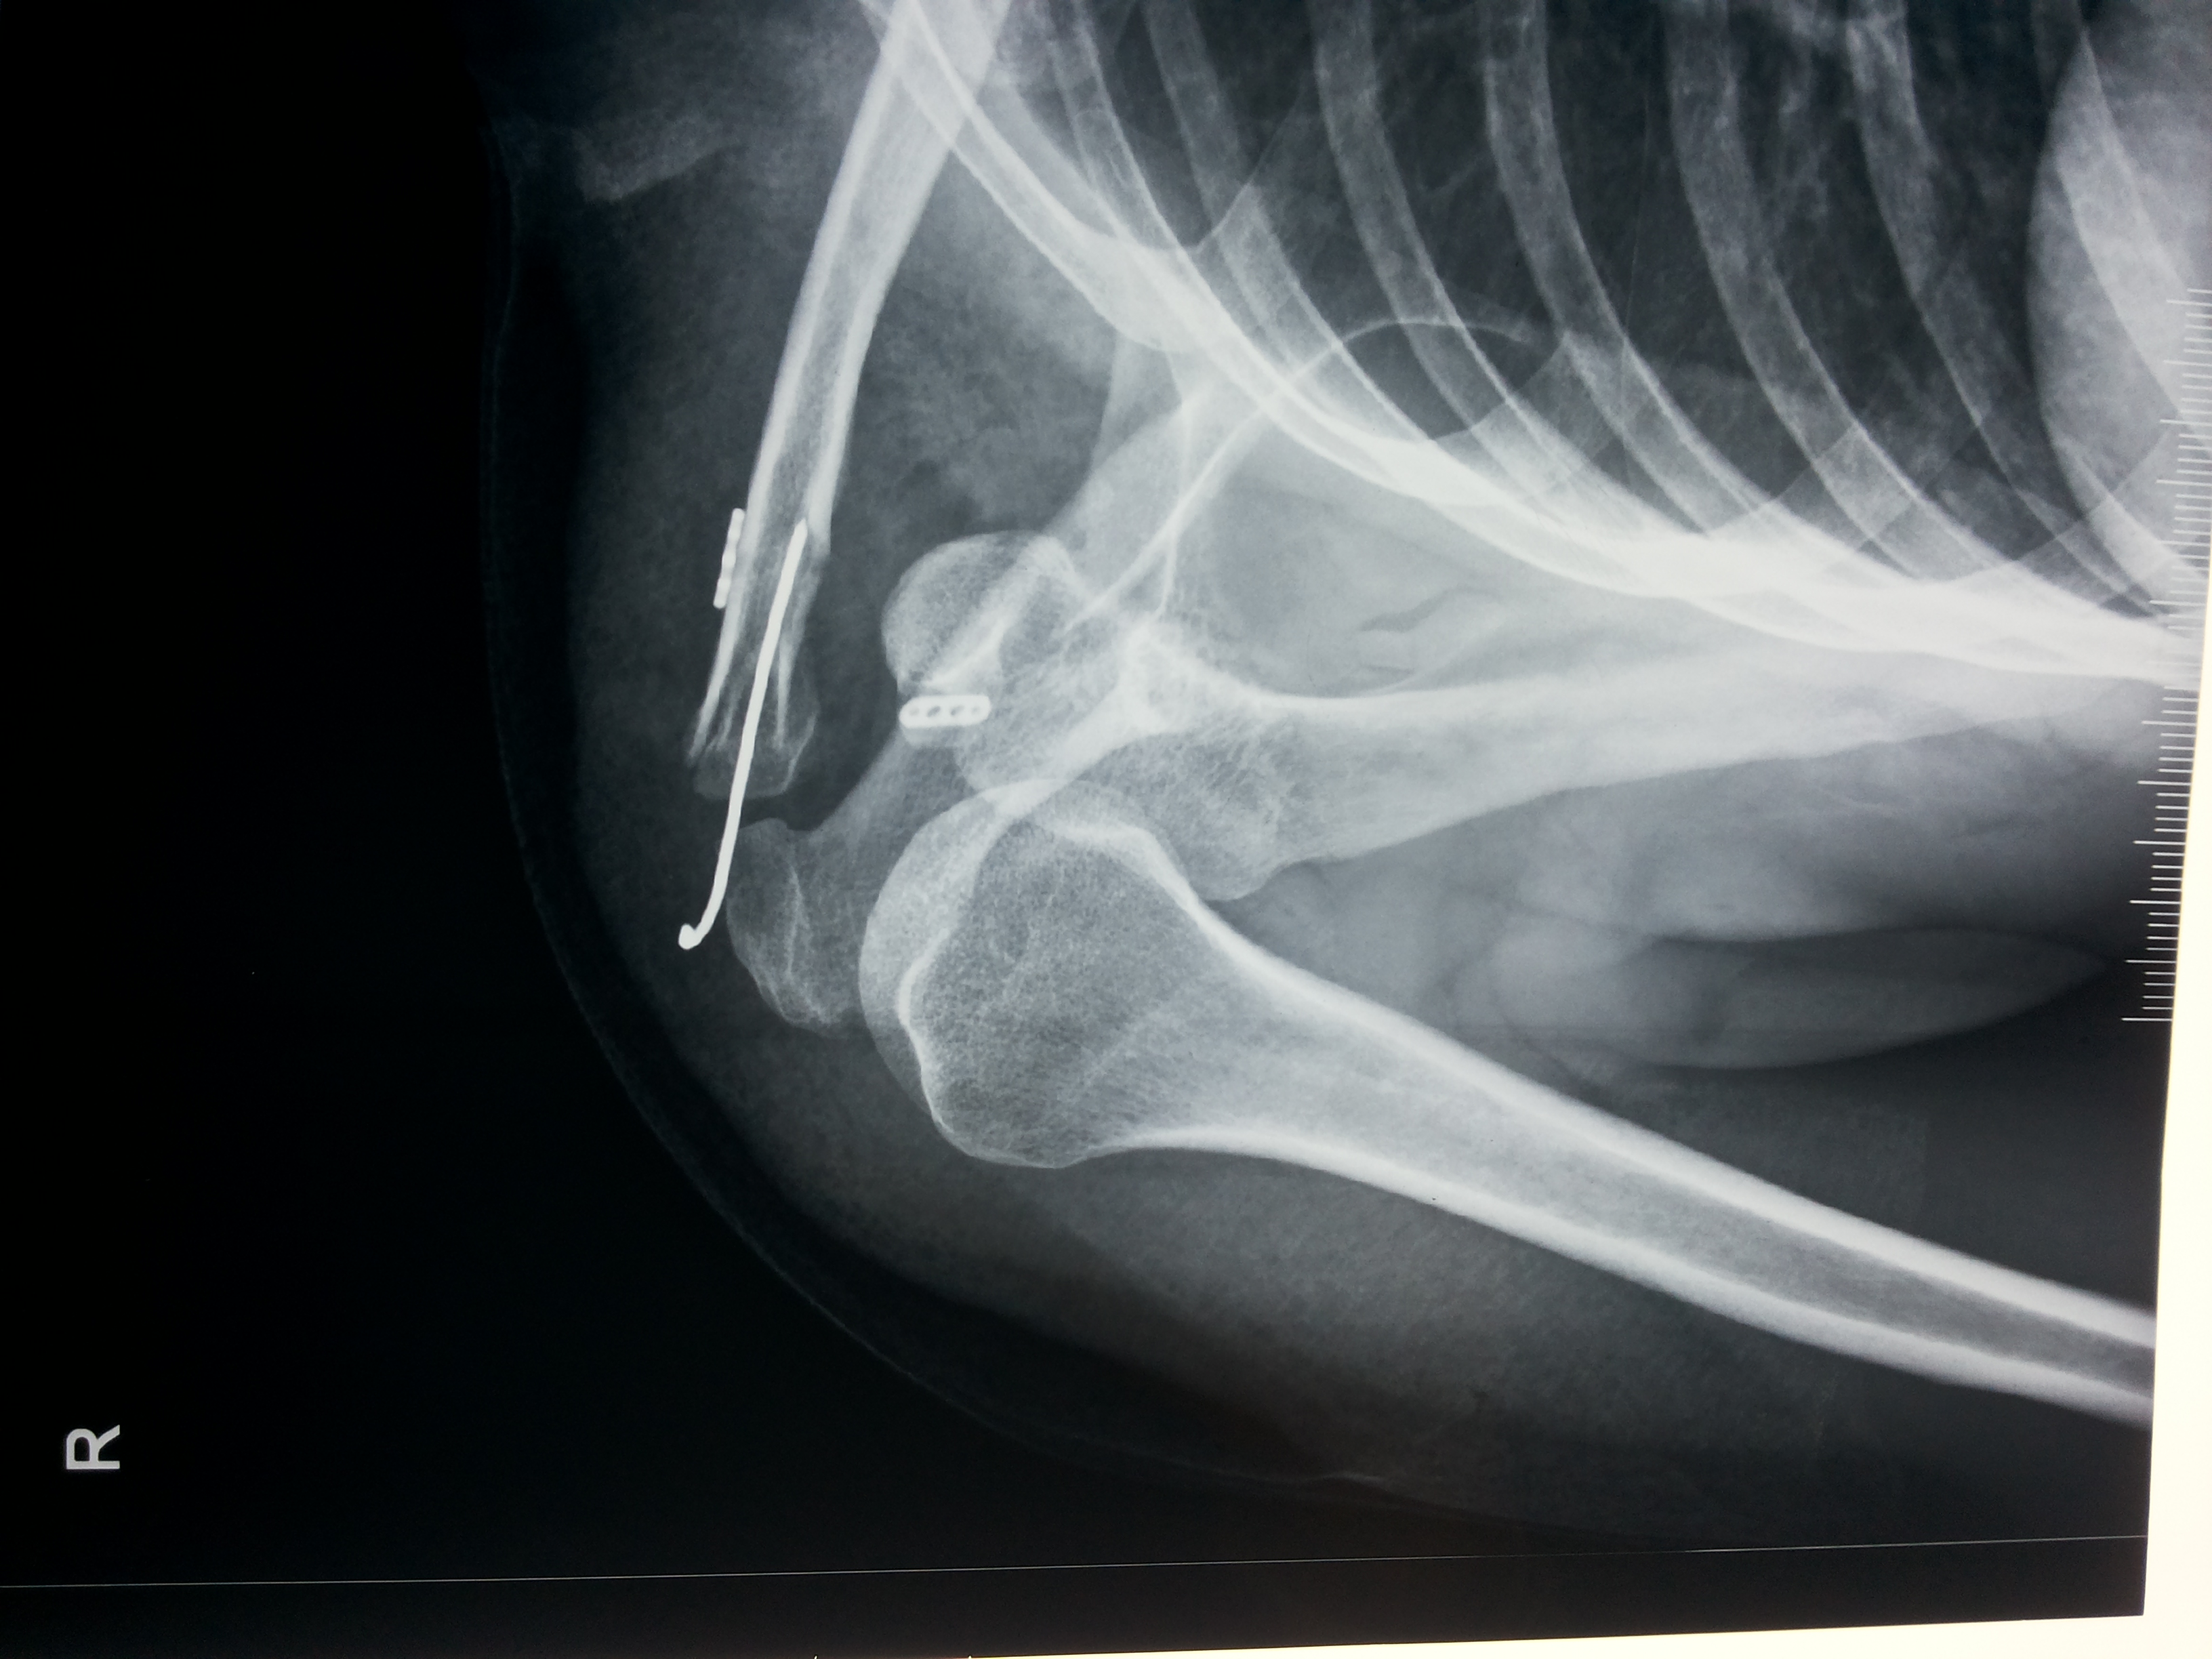

A comprehensive physical examination of the shoulder along with a detailed history and a series of x-rays will lead to a confirmed AC joint injury diagnosis. An x-ray can also help rule out any additional injuries to the bone, such as a fracture of the end of the collarbone. In addition to x-ray, an MRI scan to determine the injury grade and assess injury of surrounding ligaments to arrive at an effective and individualized treatment plan.

Imaging including x-rays and MRI (magnetic resonance imaging) are frequently used as well. X-rays can help make sure that the shoulder is located within the socket, and evaluate for any fractures. MRI can be used to determine if there are any injuries to the soft-tissues surrounding the shoulder, including the labrum. Based on all of the information gathered from the history, physical exam, and imaging, Doctor can discuss treatment options based on your goals and activity level.

Medical imaging can also be done to look at the severity of the shoulder arthritis and rule out other possible causes of pain. An X-ray of your shoulder can show if there is a loss of space between the shoulder head and the glenoid, or “socket.” A loss of joint space means there is a loss of cartilage. If X-rays do not give a clear cause, an MRI can also be done.